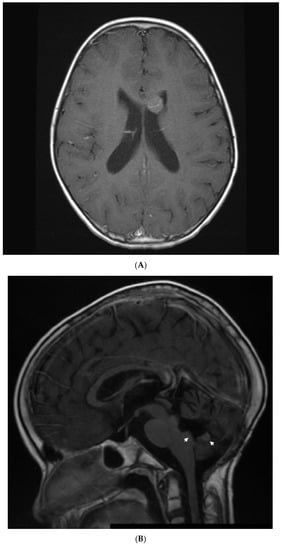

Figure 1.

Patient 1: CT with contrast shows a large 11 × 7 cm left renal tumor with retroperitoneal infiltration, regional metastatic retroperitoneal adenopathy, and extension to renal vein and inferior vena cava. The patient also had innumerable solid circumscribed masses throughout the lung parenchyma bilaterally (not shown).